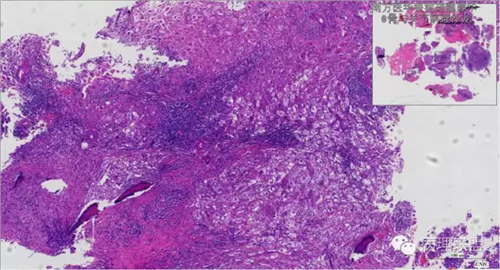

来源于组织细胞的相似性骨病ECD vs RDD 看图说话